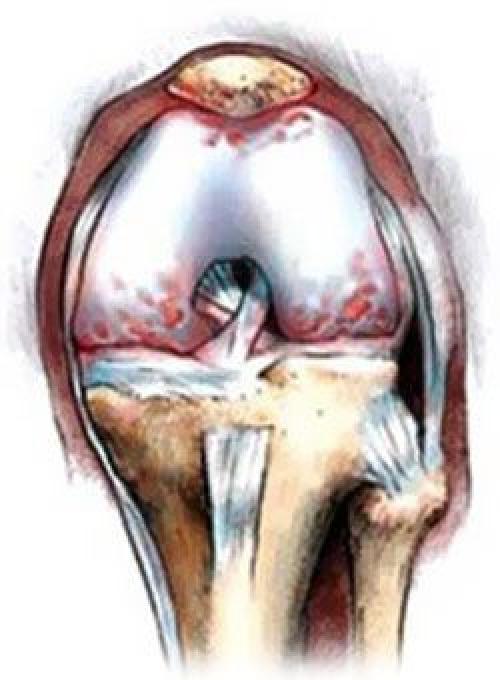

При артрозе истончается хрящевая соединительная ткань сустава, тем самым травмируя кости